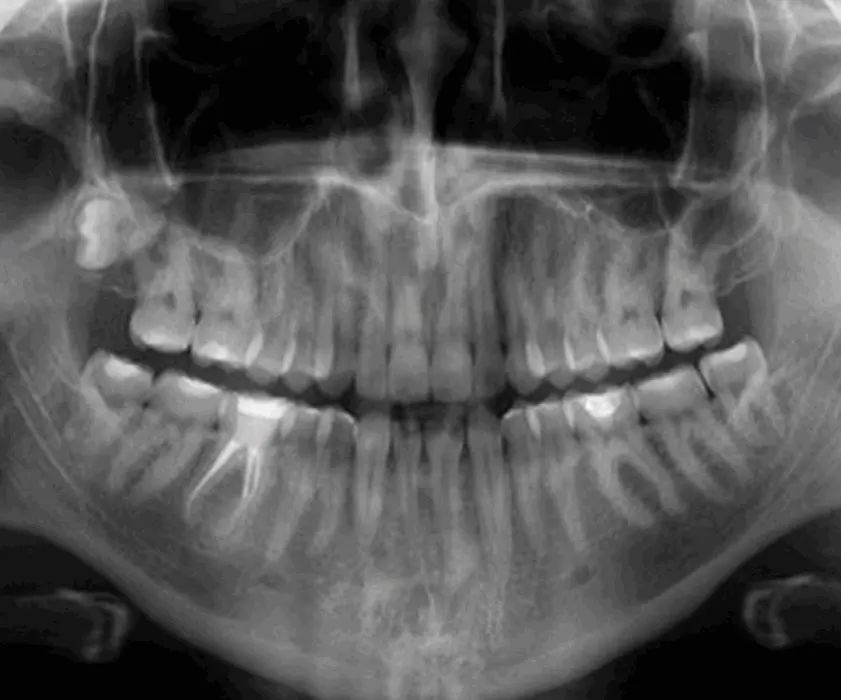

With a panoramic x-ray, the cause of the pain and swelling is visible very quickly, and the dentist will suggest the therapy during diagnostics.